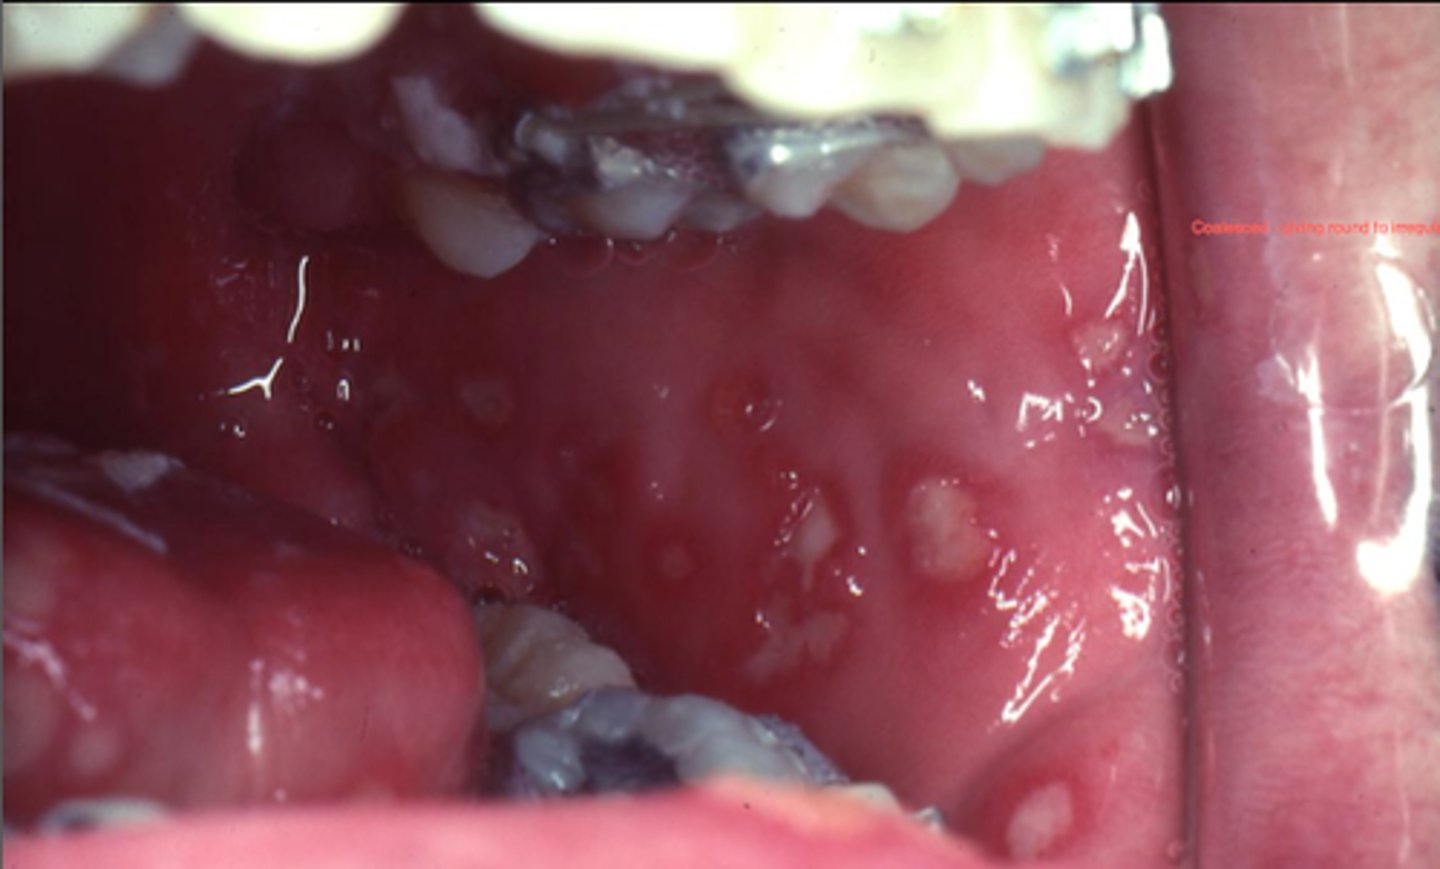

cheek chewing (morsicatio buccarum)

along occlusal

bilateral / symmetrical

shaggy